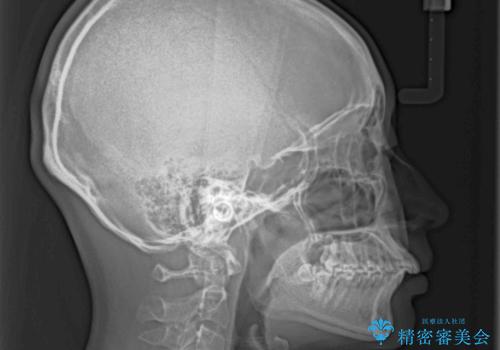

- 口を閉じたときに唇の間から飛び出してくる前歯を気にして来院された患者様です。

骨格的に上顎骨が前方位にあるため、左右の第一小臼歯を抜歯し、ワイヤー装置にて咬み合わせを整えていくこととしました。